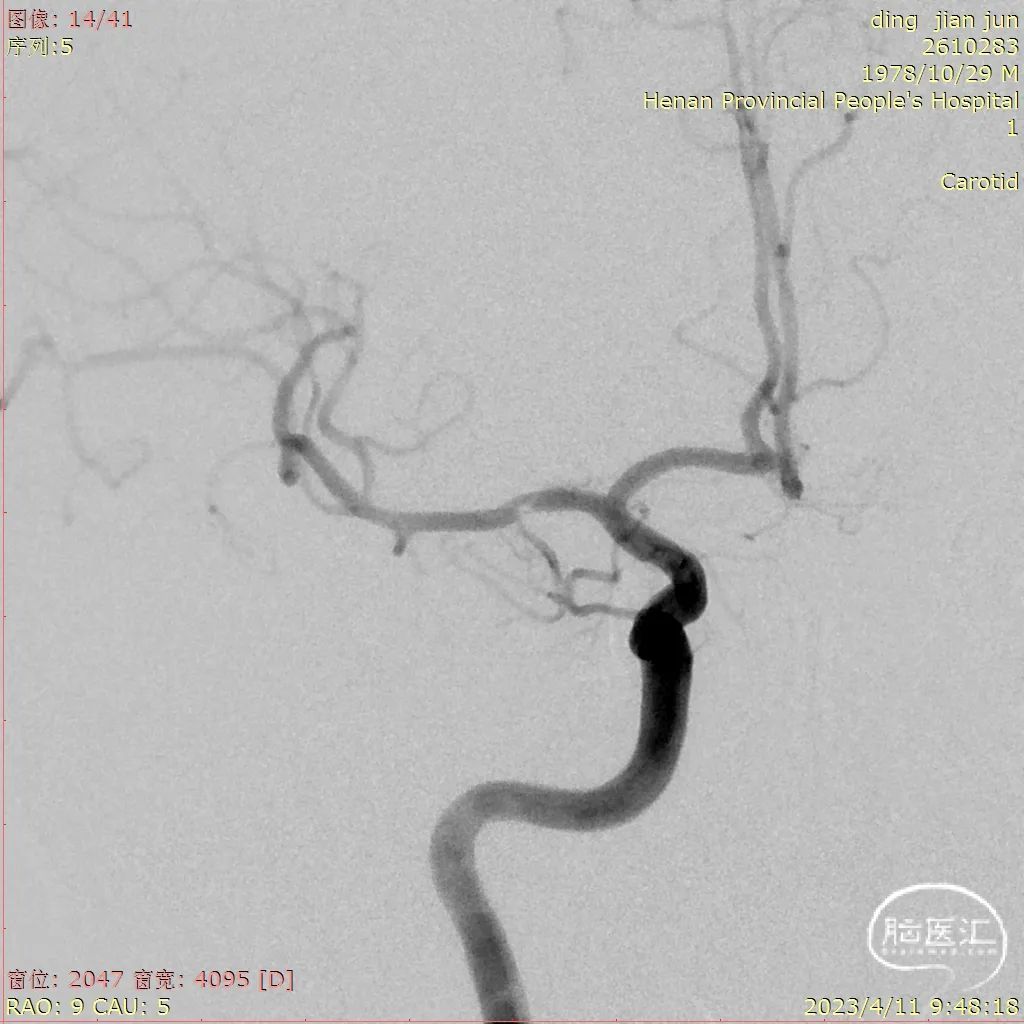

MRA提示右侧大脑中动脉M1段局限性重度狭窄。

CTA提示右侧大脑中动脉局部充盈缺损。

入院后DSA提示右侧大脑中动脉充盈缺损,考虑夹层可能大。

置入3.5*15mm 颅内支架,造影显示支架完全打开,贴壁良好。

术后即刻造影显示狭窄明显缓解。